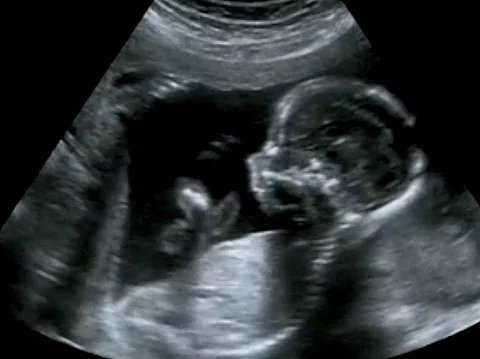

Inwieweit hat sich die Corona-Pandemie auf die Sicherheit von Müttern und Kindern während der Schwangerschaft ausgewirkt? Diese Frage stand im Mittelpunkt einer Studie, die ein Team um Rose Molina vom Department of Obstetrics and Gynecology am Beth Israel Deaconess Medical Center in Boston durchgeführt hat.